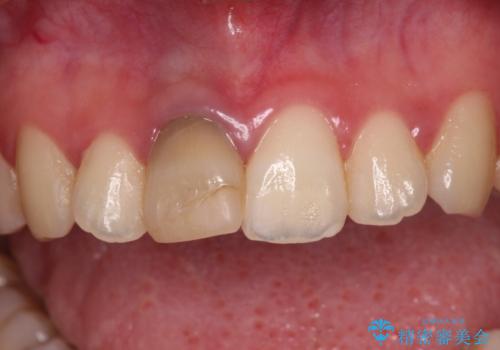

- 虫歯により神経を取り除いた前歯の変色が気になるとのことで来院された患者様です。

レントゲン写真より、歯根の炎症が認められなかったため、ファイバーコアによる土台築製後、オーダーメイドタイプのオールセラミッククラウンにて補綴することとしました。